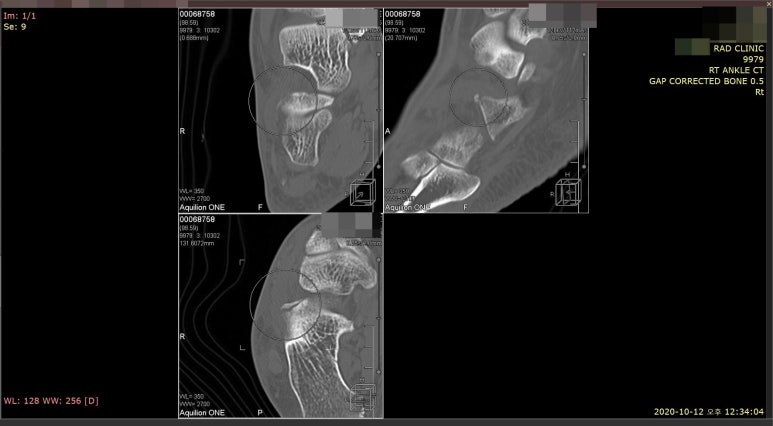

## 엑스레이를 꼼꼼하게 살펴보니 골절선이 명확하게 보이지 않았습니다.환자분의 발목에서 부어있는 곳을 2mm단위로 바둑판처럼 촘촘하게 하나 하나 눌러서 아픈 부위를 찾아봤습니다. 환자분께서 통증을 호소하는 곳은 종골이라는 뼈의 앞쪽 돌기였습니다. 발목을 접질렀을때 인대가 늘어나면서 파열도 잘 생기는 곳이고, 뼈를 잡아당기면서 골절도 자주 생기는 부위입니다. ## 무엇보다 제일 큰 문제는 종골 전방돌기가 엑스레이상 뼈가 겹쳐보여서 실금(미세골절), 견열골절이 잘 보이지 않는다는 것입니다. 걷는데 큰 지장이 없고, 인대를 늘려봤을 때 많이 아프지 않다고 하셔서 미세골절 가능성을 충분히 설명해드리고 MRI보다 CT 검사를 권고 드렸습니다. ## 작은 뼈 조각은 MRI에서 보이지 않기 때문에 뼈를 위주로 관찰하는 CT 검사가 골절 진단에 더 적합합니다. 만약 걷기가 어렵고 스트레스 검사상 통증이 심하다면 주변 인대, 근육, 연골 손상이나 뼈에 멍이 드는 골수 부종도 있을 수 있어 MRI 검사를 같이 실시해야 합니다. 어떤 검사를 하면 좋을지는 의학적 전문지식이 필요한 영역으로 진료의가 결정해드립니다..그러니까 크게 고민하지 않으셔도 괜찮습니다.

골절의 가능성이 있으므로 비탄력 테이핑으로 발목을 단단하게 고정하고 협력병원으로 즉시 CT검사를 의뢰하였습니다. ## X-ray를 찍은지 2시간 뒤인 12시반쯤 시행한 CT검사에서 종골 전방돌기의 골절로 진단되었습니다.

위 사진처럼 발등 골절이 좌측 X-ray에서 보이지 않았지만, 우측 CT에서는 보입니다.초기 미세골절, 견열골절, 실금은 단순 방사선 검사인 엑스레이에서 잘 보이지 않습니다.그렇다고 CT가 완전한 골절 진단법일까요?아닙니다. 연식이 오래된 예전 CT 검사에서는 2mm 이하의 작은 뼈 조각은 안 보일 때도 있습니다. 그래서 가급적 최신 640 CT나 초음파검사로 골절 의심부위를 촘촘하게 단면을 확인해보는 것이 좋습니다.**